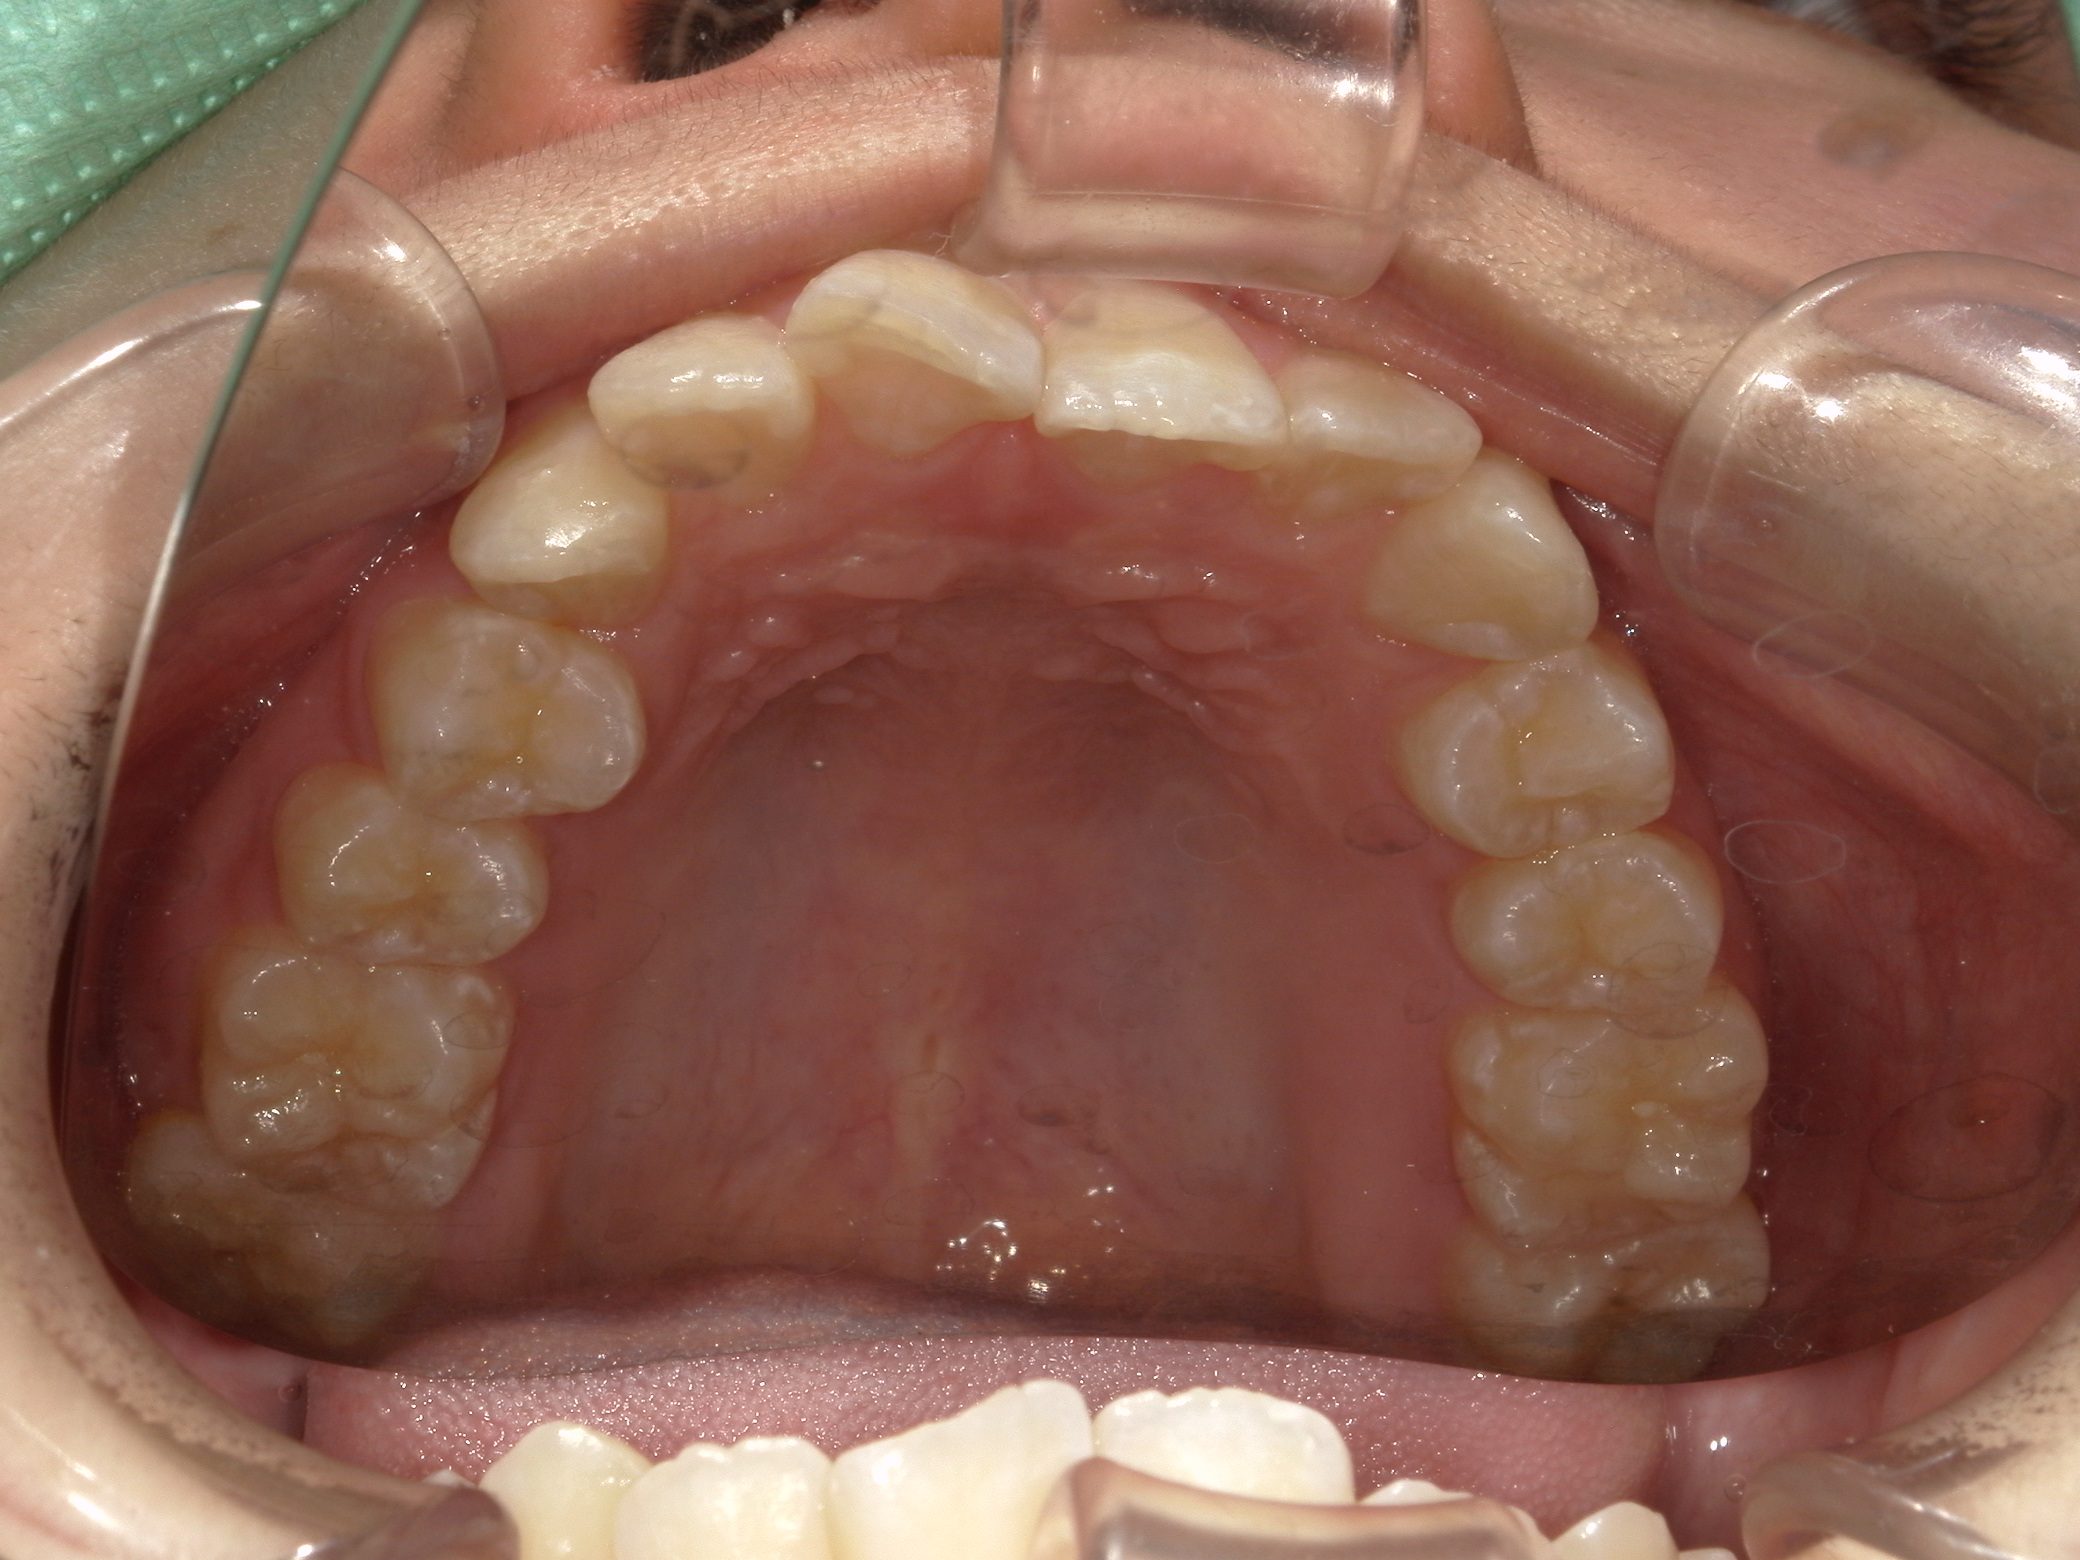

【中学生】インビザラインフル 上顎前突(出っ歯)と 叢生(でこぼこ) を改善

小学生で開始

インビザライン フル

でこぼこ

出っ歯

過蓋咬合

非抜歯

2期治療のみ

Before

After

治療期間

2年

治療開始

14歳

種類

インビザライン矯正

使用装置

インビザラインフル

コメント

先天欠損歯がある患者さんです。

途中 留学されたので 治療を進める速さを遅くした時期もありました。

しっかりはめてくれて 奥歯の咬み合わせも改善し治っています。